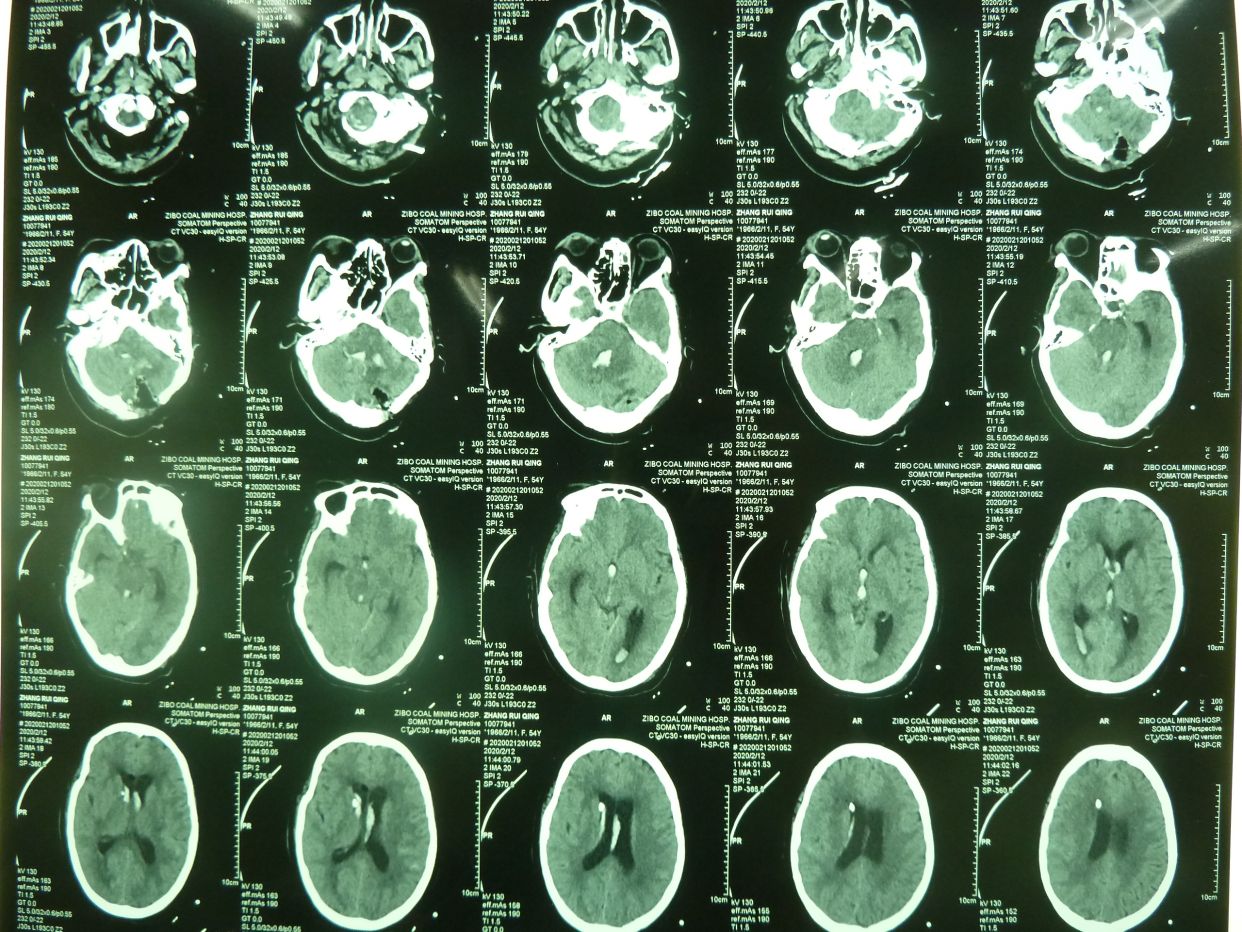

例2,患者女,54岁,突发头痛并意识不清3小时入院,有高血压、冠心病史多年,深昏迷,入院时出现呼吸停止,行气管插管,机械辅助呼吸。

CT示,小脑大量出血破入全脑室并梗阻性脑积水,与家属沟通并签字后急症行脑室外引流术,后颅凹开颅血肿清除术。

术后1天CT复查示,血肿清除满意,基底池可见,患者刺激睁眼。

患者术后1月,神志清,正确回答问题,四肢话动良好,出院康复。